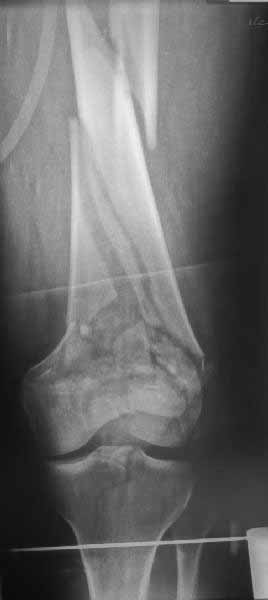

Re: перелом бедра

Вы затрагиваете слишком глобальные вопросы. Чтобы дать аргументированные ответы на них, необходимо коснуться основных принципов интерлокинга. Безусловно, это моё персональное мнение, основанное на личном практическом опыте и доступных мне теоретических сведениях и, может быть, в некоторой степени, не совпадающее с общепринятыми положениями. Прошу прощения за излишне длинный пост и освещение общеизвестных фактов. Существует два способа создания биомеханической системы интрамедуллярный стержень – сломанная длинная трубчатая кость. Первый способ был предложен основателем интрамедуллярного остеосинтеза Герхардом Кюнчером. Когда мы вводим какой-либо объект (стержень) в какую-либо структуру (длинную трубчатую кость), оказывается определённое давление на эту структуру, которое вызывает обратное давление на этот объект и таким образом образуется упругое взаимодействие между структурой и объектом. Кюнчер использовал эту фундаментальную идею, когда поместил стержень в костномозговой канал. Стержень имел форму трилистника в поперечном сечении и продольный разрез по всей длине стержня. Поперечное сечение стержня было шире, чем костномозговой канал, что позволяло стержню при введении деформироваться и плотно прилегать к стенкам костномозгового канала и тем самым обеспечивать стабильную фиксацию. Однако надёжность фиксации при таком способе достигалась только на уровне истмуса. Проблемной оставалась ротационная стабильность. Всё это привело к появлению блокированных стержней. Диаметр их меньше диаметра костномозгового канала, что облегчает введение. Кроме того, благодаря более толстым стенкам самих стержней, отсутствию продольного разреза и блокировочным винтам надёжность фиксации переломов значительно повышается, причём вне зависимости от их вида. Появилась возможность обеспечит стабильную фиксацию супра- и инфраистмальных переломов. Изменилась философия создания биомеханической системы «стержень-кость». Вместо плотного прилегания стержня к стенкам костномозгового канала, кость и стержень соединяются между собой с помощью блокирующих винтов, образуя при адекватном блокировании биомеханическую систему с высоким уровнем стабильности. В этой системе одинаково важное значение имеют прочностные характеристики трёх элементов: стержня, блокирующих винтов и того участка самой кости, где они расположены. Если взять за аксиому, что металлоконструкции изготовлены из качественного металла, то прочность стержня будет зависеть от его диаметра, а прочность блокирующих винтов от их диаметра и количества (не менее двух, лучше в разных плоскостях при инфраистмальных переломах). Поэтому в достижении адекватной стабильности создаваемой биомеханической системы остаются критически важными прочностные характеристики третьего элемента этой системы - самой кости дистального отломка, в которой располагаются блокирующие винты. И если они достаточны, и размер дистального отломка (даже реконструированного с адекватной фиксацией) подходит для расположения необходимого количества блокирующих винтов, то не имеет абсолютно никакого значения какой у вас перелом: диафизарный, метафизарный или даже эпифизарный. Всё это условные названия анатомических областей кости. Основополагающее, ключевое значение имеют два вышеупомянутых фактора. Возможность реализации этих двух факторов зависти от адекватного информационного обеспечения (качественные рентегнограммы и особенно КТ места проведения блокирующих винтов) и от личного опыта хирурга. Безусловно, при внутрисуставных переломах первостепенное значение должно уделяться точной анатомической репозиции суставной поверхности. Но если после её выполнения появляется возможность реализовать два вышеупомянутых требования, то не должно существовать непреодолимых препятствий для фиксации перелома самым лучшим на сегодняшний день способом – блокированным остеосинтезом. Он лучший по определению. Стержень располагается в центре механической нагрузки. Только один этот факт (а есть ещё много других) перевесит все достоинства любого накостного остеосинтеза в плане надёжности фиксации и возможности ранней нагрузки, в том числе пластинок с угловой стабильностью. Кстати, блокирующие винты в стержне являются более мощным препятствием для возникновения угловых деформаций дистального отломка, чем винты в пластинке с угловой стабильностью. Их угловая стабильность обеспечена поперечным каналом в стержне, длиной, как правило, более 1 см посередине блокирующего винта, а не 2-3 витками резьбы на головке винта на его одном конце. Это к вопросу о «риске вторичного смещения».

Однако в случае, представленном Константином Никитиным, не может быть применён ни ретроградный ни антеградный остеосинтез. Причина - нереально выполнить вышеуказанные необходимые требования, касающиеся дистальных блокирующих винтов. Из-за низкого перелома латерального мыщелка (перелом Hoffa) невозможно через него провести хотя бы 2 блокирующих винта, поскольку линия перелома мыщелка расположена либо на уровне верхушки межмыщелковой ямки либо незначительно проксимальнее. Поэтому авторам, с моей точки зрения, необходимо прислушаться к рекомендациям Джолдаса.